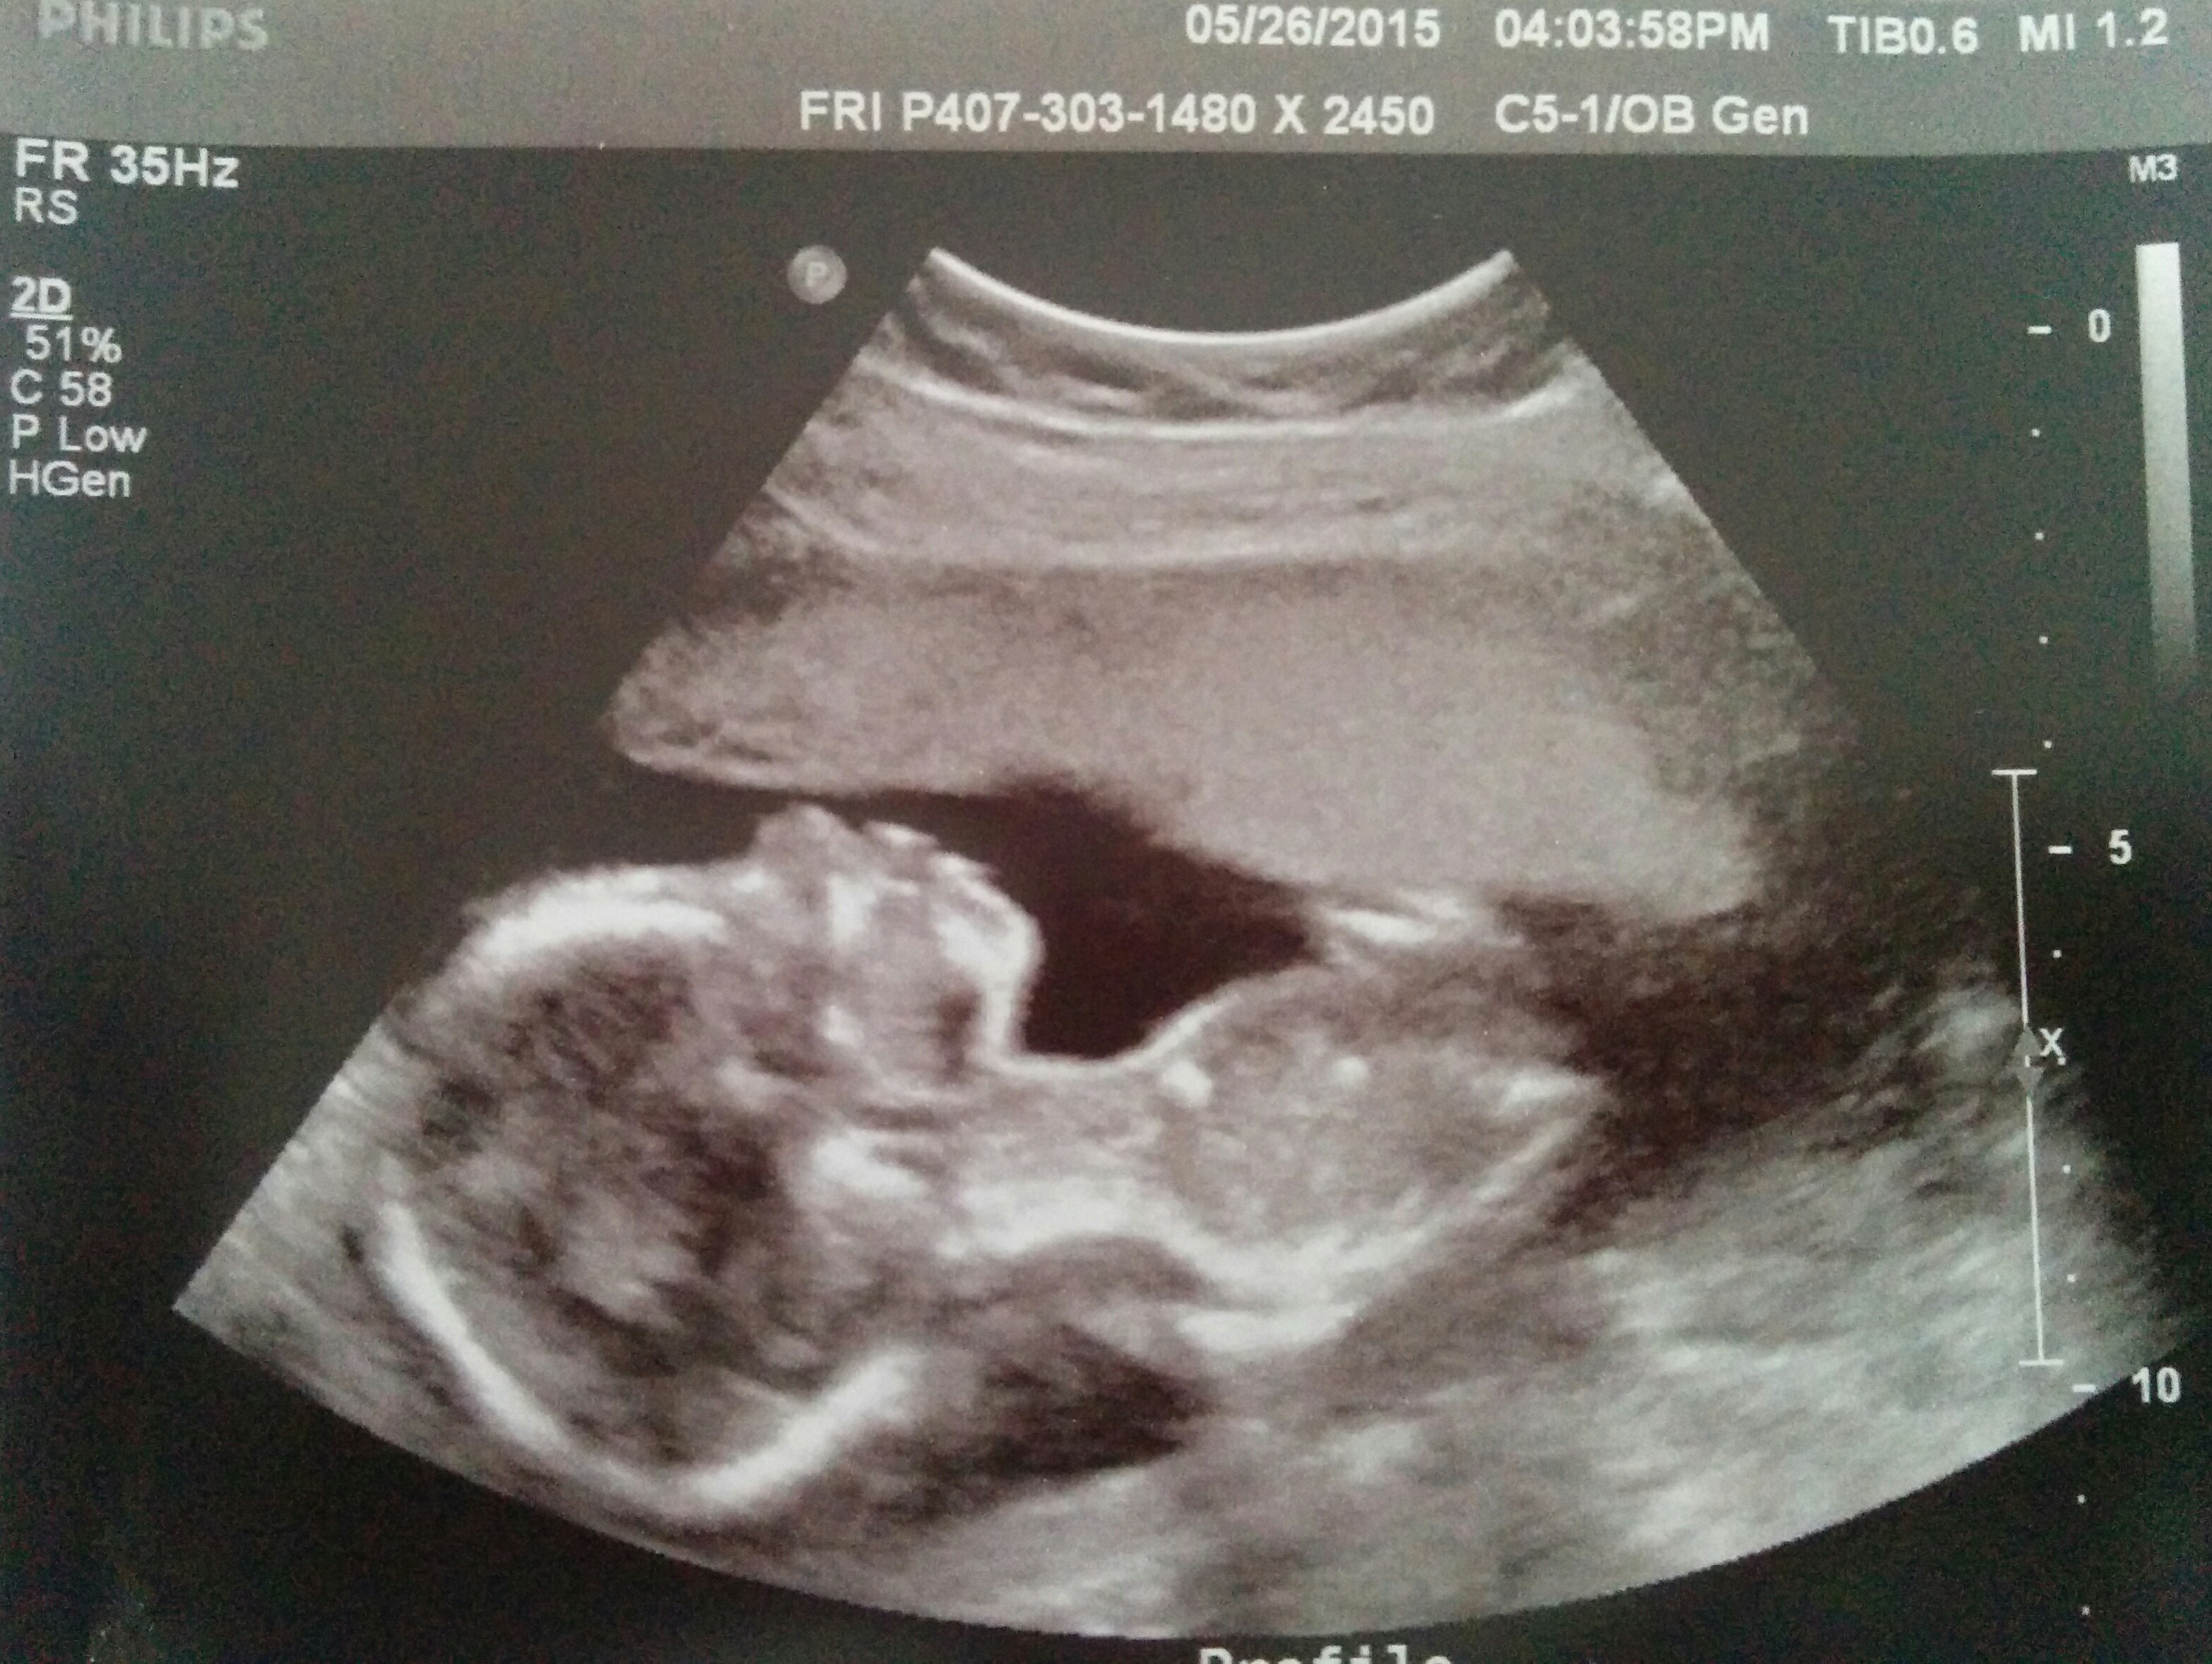

Introducing Baby C at 19 weeks!